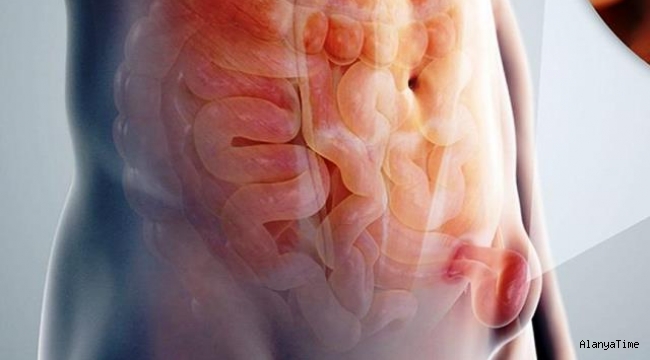

Doç. Dr. Şimşek, sözlerine şöyle devam etti: "İnguinal herni olarak tanımlanan kasık fıtığı, karın duvarı fıtıkları içinde en sık teşhis edilen fıtık türüdür. Kasık fıtığı, kasık bölümünde yer alan karın duvarının zayıf noktasından karın içindeki organların periton ile birlikte dışarıya doğru çıkmasıdır. Görülme sıklığı bilinmemekle birlikte yaklaşık olarak erkeklerin üçte biri hayatlarının bir döneminde fıtık operasyonu geçirirler. İnguinal herniler özellikle 50 yaş üzeri erkeklerde çok yaygındır. Kadınlarda bu oran daha azdır. Kasık fıtığı tüm fıtıklar içinde yüzde 80 oranıyla en sık görülen fıtık tipidir".

Doç. Dr. Şimşek, kasık fıtığının nedenlerinden bahsederek, "Doğumsal ve edinsel olabilir. Kronik kabızlık, prostat hastalıkları nedeniyle oluşan zorlu idrara çıkma. Karın içi basıncın artması. Kronik hale dönüşen öksürük ve hapşırma durumu. Ağır kaldırma, karın içerisinde sıvı birikmesi, edinsel kasık fıtığına en sık neden olan faktörlerdir. Belirtileri ise; kasık bölgesinde ele gelen şişlik, öksürme ve hapşırma durumlarında kasık bölgesinde ağrı, erkeklerde kasık bölgesinde başlayıp skrotuma doğru yayılan ağrı olarak görülebilir. Kasık fıtığı tedavisinde uygulanan tek yöntem cerrahi müdahaledir, ilaç ile tedavi seçeneği yoktur. Cerrahi müdahale açık veya laparoskopik olarak uygulanabilir. Açık ameliyatta kişinin kasık bölgesine yaklaşık 5-6 cm uzunluğunda kesi uygulanır. Laparoskopik uygulamada ise 3 küçük kesi yeterlidir. Bu kesiler sayesinde içeri bir kamera sokulur ve ameliyat gerçekleştirilir" ifadelerini kullandı.

Her iki ameliyat türünde de fıtıklı bölgenin içindeki organların tümünün karın içine alındığını söyleyen Doç. Dr. Şimşek, "Fıtık bölgesi mesh adı verilen bir malzeme ile onarılarak tekrar fıtık oluşumu engellenir. Ameliyat sonrası hastalık tekrarı görülebilir. Bu oran yüzde 2 civarındadır. Ameliyat tekniğine ve hastanın kendi mevcut faktörlerine bağlı olarak gelişebilir. Kasık fıtığı tedavi olunması gerekli bir hastalıktır. Tedavi edilmediği sürece iyileşme olmaz. Halk arasında fıtığın sıkışması olarak bilinen durum acil müdahale gerektirir. Fıtık kesesine giren karın içi organların sıkışması sonucu karın içi yerlerine dönememeleri durumudur. Hasta bunu şişliğinin el ile bastırma sonucunda inmediği şeklinde ifade eder. En yakın sağlık kuruluşuna başvurmayı gerektiren bir durumdur. Kasık fıtığı ileri yaşla birlikte görülme sıklığı artan bir hastalıktır. Aynı zamanda ileri yaştaki hastalarda yandaş hastalıkların görülme sıklığı artmaktadır. Yandaş hastalıkların tanısına göre ameliyat riski artabilir. Kasık fıtığında açık yöntem ile yapılan operasyonlarda hastanın genel durumu ve ek hastalıklarının ciddiyetine göre lokal anestezi şekli uygulanabilmektedir" açıklamalarında bulundu.